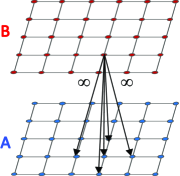

Metrication error: Metrication error, also known as grid bias, is defined as the artifacts which appear in graph-based segmentation methods due to penalizing region boundaries only across axis aligned edges. ¡ltx:note¿Figure 3 compares the discrete and continuous version of a max-flow algorithm. As seen in Figure 3, the contours obtained by graph cuts are noticeably blocky in the areas with weak regional cues (weak data term), while the contours obtained by the continuous method are smooth.¡/ltx:note¿ The discrete nature of graph-based methods makes it difficult to efficiently implement a convex regularizer like total variation in the discrete domain. Metrication error can be reduced in graph-based methods by increasing the graph connectivity, e.g. (Boykov and Kolmogorov, 2003), but that also increases memory usage and computation time. In contrast, within the continuous domain, there is no such limitation and regularizers can be implemented efficiently that makes the PDE approaches free from metrication error. Note that although approaches with continuous energy formulations do not induce metrication errors, due to the discrete nature of digital images, all continuous operations are estimated by their discrete versions in the implementation stage.

(a) GF

(b) CCMF

(c)

(d)

(e)

(f) Figure 3: ¡ltx:note¿Metrication artifacts. Brain segmentation using (a) classical max-flow algorithm or graph cuts (GC) and (b) combinatorial continuous max-flow (CCMF) (Couprie et al., 2011). (c,e) Zoomed regions of (a). (d,f) Zoomed regions of (b).

(Images adopted from (Couprie et al., 2011))¡/ltx:note¿ -